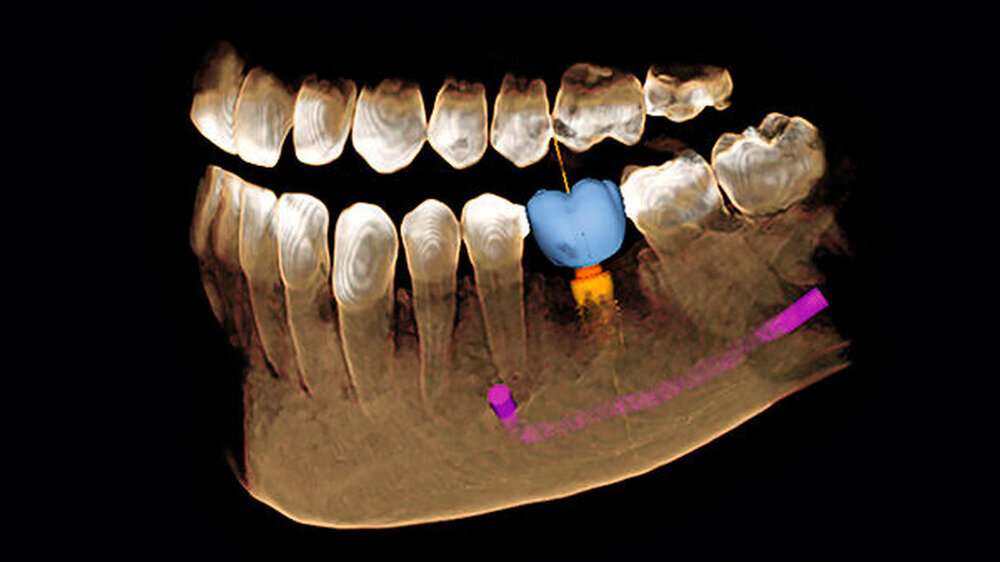

Die Investition in einen digitalen Volumentomografen liegt mit rund 70.000 Euro etwa doppelt so hoch wie bei Top-2-D-Geräten. Die Aufnahmen erleichtern fast jede Diagnose oder Behandlung - von der Wurzelspitzenresektion über den lokalen Knochenaufbau bis hin zum Sinuslift. Fortgeschrittene Systeme schaffen auch die Anbindung an die geführte Chirurgie (Bohrschablonen), teilweise sogar ohne die Notwendigkeit von Abdrücken oder Gipsmodellen. Dadurch wird die Entwicklung von einer primär am Knochenangebot orientierten zu einer von der Prothetik her geplanten implantologischen Behandlung befördert.

Im „digitalen Extremfall“ reichen eine Aufnahme mit dem Intraoralscanner, ein daraus abgeleitetes CAD-Design und dessen Überlagerung mit 3-D-Röntgen-Daten. Auf der Grundlage dieses Inputs kann der Behandler zum Beispiel eine Implantatplanung ganzheitlich angehen, das heißt Knochenangebot und Prothetik am Bildschirm gleichzeitig optimieren. Selbst das gewünschte Emergenzprofil kann dabei schon berücksichtigt werden.